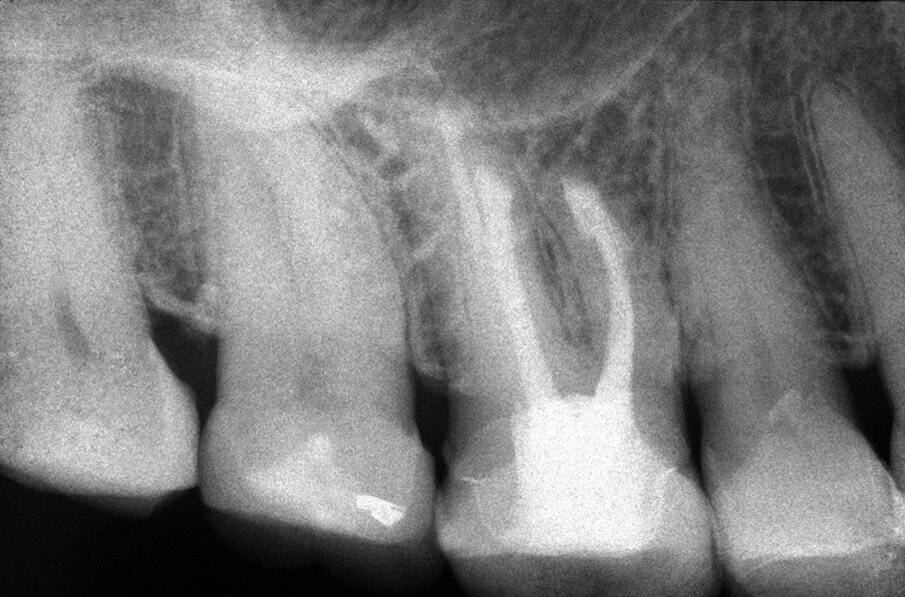

Tali perforazioni sono piuttosto frequenti a livello degli incisivi superiori, dove l’errore che più spesso viene commesso è rappresentato dall’utilizzo della fresa con eccessiva angolazione vestibolare. Perforazioni del terzo coronale possono anche accadere sul pavimento dei molari quando gli orifizi canalari vengono cercati in posti sbagliati. Tipiche sono le perforazioni nei molari superiori o inferiori, che avvengono per lo sfondamento del pavimento della camera pulpare (Figg. 3a-3i). Come conseguenza del trauma meccanico, si ha una rapida distruzione del legamento parodontale. L’osso alveolare immediatamente adiacente alla perforazione si riassorbe con conseguente perdita verticale di osso. Il processo infiammatorio quindi si estende coronalmente lungo le fibre del legamento parodontale, con distruzione del legamento, dell’osso alveolare e delle fibre gengivali sopracrestali. Come conseguenza di ciò, si ha la migrazione apicale dell’attacco epiteliale e le formazione di un grave difetto parodontale9.